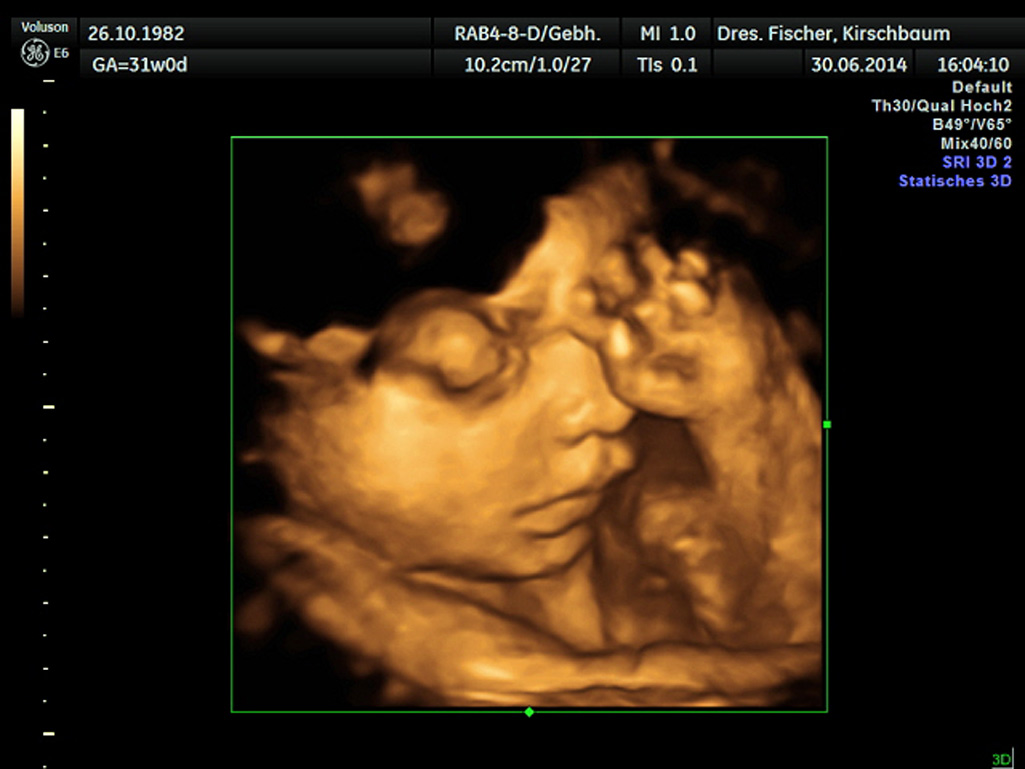

Bilder waren gestern – heute gibt es Video. Unser hochauflösendes Ultraschallgerät erzeugt bewegte dreidimensionale Bilder in Echtzeit. Das Ergebnis sind beeindruckende Bewegtbilder des ungeborenen Kindes zu diagnostischen Zwecken.